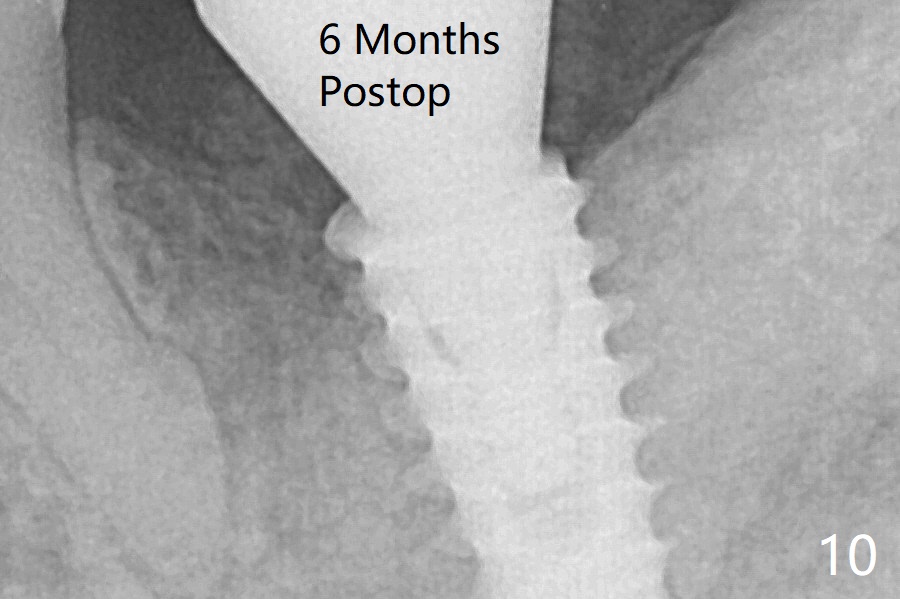

In fact the mesial crest is resorbed 3.5 months postop (Fig.9 M, as compared to that of preop and immediate postop in Fig.0,1). Continuous resorption may be associated with food impaction when a permanent crown is delivered. The mesial crest does not look so atrophic 6 months postop (Fig.10). The preventive remedy would be socket shield, mesial and distal (Fig.0' M, D).